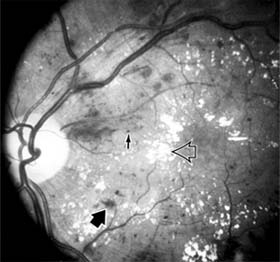

Chapter 10: Retina RETINAL VASCULAR DISEASES DIABETIC RETINOPATHY Diabetic retinopathy is one of the leading causes of blindness in the Western world. The view that chronic hyperglycemia of diabetes mellitus is the major determinant of diabetic retinopathy is supported by the observation that retinopathy in young people with type I (insulin-dependent) diabetes does not occur for at least 3-5 years after the onset of this systemic disease. Similar results have been obtained for type II (non-insulin-dependent) diabetes, but in such patients the time of onset and therefore the duration of disease are more difficult to determine precisely. It is recommended that patients with type I diabetes mellitus be referred for ophthalmologic examination within 3 years after diagnosis and reexamined on at least an annual basis. Type II diabetic patients should be referred for ophthalmologic examination at the time of diagnosis and reexamined at least annually. As diabetic retinopathy can become particularly aggressive during pregnancy, any diabetic woman who becomes pregnant should be examined by an ophthalmologist in the first trimester and at least every 3 months thereafter until parturition. In terms of both prognosis and treatment, it is useful to divide diabetic retinopathy into nonproliferative and proliferative categories. The prevalence of proliferative retinopathy in type I diabetics with 15 years of systemic disease is 50%. While the prevalence of proliferative disease at 15 years is much less in type II diabetics, the prevalence of macular edema as a function of the duration of systemic disease is the same in both groups. 1. NONPROLIFERATIVE DIABETIC RETINOPATHY Diabetic retinopathy is a progressive microangiopathy characterized by small vessel damage and occlusion. The earliest pathologic changes are thickening of the capillary endothelial basement membrane and reduction of the number of pericytes. Background diabetic retinopathy is a clinical reflection of the hyperpermeability and incompetence of involved vessels. The capillaries develop tiny dot-like outpouchings called microaneurysms, while the retinal veins become dilated and tortuous (Figure 10-20). Multiple hemorrhages may appear throughout different levels of the retina. Flame-shaped hemorrhages are so shaped because of their location within the horizontally oriented nerve fiber layer, while dot and blot hemorrhages are in the deeper retina, where cells and axons are vertically oriented. Macular edema is the most frequent cause of visual loss among patients with background diabetic retinopathy. The edema is caused primarily by a breakdown of the inner blood-retinal barrier at the level of the retinal capillary endothelium, allowing leakage of fluid and plasma constituents into the surrounding retina. The edema may be focal or diffuse and appears clinically as thickened, cloudy retina with associated microaneurysms and intraretinal exudate. Circinate zones of yellow, lipid-rich exudate may form around clusters of microaneurysms and are most frequently centered in the temporal portion of the macula. While the prevalence of macular edema is 10% in the diabetic population as a whole, there is a dramatic increase in prevalence in eyes with more severe retinopathy. With progressive microvascular occlusion, signs of increasing ischemia may be superimposed on the picture of background retinopathy and produce the clinical picture of preproliferative diabetic retinopathy. The most typical findings here are multiple cotton-wool spots, beading of the retinal veins, and irregular segmental dilation of the retinal capillary bed (intraretinal microvascular abnormalities). Closure of retinal capillaries surrounding the foveal avascular zone may cause significant ischemia, manifest clinically by the presence of large dark retinal hemorrhages and small thread-like macular arterioles. Eyes with macular edema and significant ischemia have a poorer visual prognosis-with or without laser treatment-than eyes with edema and relatively good perfusion. The visual and electrophysiologic dysfunctions associated with diabetes probably result from the local vascular abnormalities and the systemic metabolic effects of the disease to which the retina is subjected. A characteristic blue-yellow color vision abnormality develops, and hue discrimination may be impaired. Contrast sensitivity may be reduced in patients, even in the presence of normal visual acuity. Visual field testing may show relative scotomas corresponding to areas of retinal edema and nonperfusion, and abnormalities in dark adaptation have also been described. Electroretinographic abnormalities bear a relationship to the severity of retinopathy and may aid in predicting progression of retinopathy. Fluorescein angiography is invaluable in defining the microvascular abnormalities of diabetic retinopathy (Figures 10-21 and 10-22). Large filling defects of capillary beds-"capillary nonperfusion"-show the extent of retinal ischemia (Figure 10-23) and are usually most prominent in the midperiphery. The fluorescein leakage associated with retinal edema may assume the petaloid configuration of cystoid macular edema or may be diffuse. Other fluorescein abnormalities include vascular loops and intraretinal shunts. The focus of treatment in patients with nonproliferative diabetic retinopathy and no macular edema is treatment of hyperglycemia and intercurrent systemic disease. A controlled clinical trial has shown that aldose reductase inhibitor therapy does not prevent progression of diabetic retinopathy. Focal argon laser treatment of discrete points of retinal leakage in patients with clinically significant macular edema, principally defined as thickening of the retina at or within 500 2. PROLIFERATIVE DIABETIC RETINOPATHY The most severe ocular complications of diabetes mellitus are associated with proliferative diabetic retinopathy. Progressive retinal ischemia eventually stimulates the formation of delicate new vessels that leak serum proteins (and fluorescein) profusely. Neovascularization is frequently located on the surface of the disk and at the posterior edge of the peripheral zones of "nonperfusion" (Figures 10-24 and 10-25). Iris neovascularization, or rubeosis iridis, can also result. The fragile new vessels proliferate onto the posterior face of the vitreous and become elevated once the vitreous starts to contract away from the retina. If the vessels bleed (Figure 10-26), massive vitreous hemorrhage may cause sudden visual loss. Eyes in which posterior vitreous detachment is complete are at less risk of developing neovascularization and vitreous hemorrhage. In eyes with proliferative diabetic retinopathy and persistent vitreoretinal adhesions, elevated neovascular fronds may undergo fibrous change and form tight fibrovascular bands that tug on the retina and exert continued vitreous contraction. This can cause either a progressive traction retinal detachment or, if a retinal tear is produced, rhegmatogenous retinal detachment. The retinal detachment may be heralded or concealed by vitreous hemorrhage. When vitreous contraction is complete in these eyes, proliferative retinopathy tends to enter the burned-out or "involutional" stage. Treatment Argon laser panretinal photocoagulation is usually indicated in proliferative diabetic retinopathy. Patients at greatest risk of significant visual loss are those with preretinal or vitreous hemorrhage or neovascularization of the disk. Panretinal photocoagulation can significantly reduce the chance of massive vitreous hemorrhage and retinal detachment in these patients by causing the regression and, in some cases, the disappearance of new vessels. The technique involves scattering up to several thousand regularly spaced laser burns throughout the retina, sparing the central region bordered by the disk and the major temporal vascular arcades (Chapter 24). Although the mechanism is not precisely understood, panretinal photocoagulation presumably works by reducing the angiogenic stimulus from ischemic retina. The role of vitreoretinal surgery in proliferative diabetic eye disease continues to evolve. Conservative management of monocular vision impairing diabetic vitreous hemorrhage in the binocular patient had been to allow spontaneous resolution over the course of several months. The results of a 4-year study designed to assess the role of early vitrectomy for severe vitreous hemorrhage and proliferative diabetic retinopathy support this surgery as a means by which good vision may be restored or maintained. The role of vitreoretinal surgery in the treatment of diabetic traction retinal detachment is described elsewhere in this chapter. CENTRAL RETINAL ARTERY OCCLUSION The patient with central retinal artery occlusion routinely relates a history of painless catastrophic visual loss occurring over a period of seconds; antecedent transient visual loss (amaurosis fugax) may be reported. The visual acuity ranges between counting fingers and light perception in 90% of eyes at the time of initial examination. An afferent pupillary defect can appear within seconds after retinal arterial obstruction, preceding the fundus abnormalities by an hour. Ophthalmoscopically, the superficial retina becomes opacified except in the foveola, where a cherry-red spot is evident (Figure 10-27). The cherry-red spot is pigment of the choroid and retinal pigment epithelium viewed through the extremely thin overlying foveolar retina and contrasted with the thicker and translucent perifoveolar retina. Twenty-five percent of eyes with central retinal artery occlusion have cilioretinal arteries that spare macular retina and may preserve some central visual acuity. Clinically, the retinal opacification resolves within 4-6 weeks, leaving a pale optic disk as the major ocular finding. In older patients, giant cell arteritis must be excluded and if necessary treated immediately with high doses of systemic corticosteroids. Other causes of central retinal artery occlusion are arteriosclerosis and emboli from carotid or cardiac sources. These are discussed further in Chapter 15. Treatment Because irreversible retinal damage has been shown to occur after 90 minutes of complete central retinal artery occlusion in the subhuman primate model, precious little time is available in which to begin therapy. Anterior chamber paracentesis can be employed in order to decrease intraocular pressure and increase retinal perfusion. This is particularly indicated in embolic central retinal artery occlusion. Intravenous acetazolamide has been used to decrease intraocular pressure, and an inhaled oxygen-carbon dioxide mixture has been employed to induce retinal vasodilation and increase the PO2 at the retinal surface. Direct infusion of a thrombolytic agent into the ophthalmic artery can result in recovery of vision. It must be performed within 8 hours after onset of the central retinal artery occlusion, requires specific radiologic expertise, and there is a risk of cerebral infarction. Systemic anticoagulants are generally not employed. BRANCH RETINAL ARTERY OCCLUSION Branch retinal artery occlusion usually presents with sudden loss of visual field and with reduction in visual acuity if the fovea is involved. Fundus signs of retinal edema with associated cotton-wool spots are limited to the area of retina supplied by the occluded vessel. Embolic causes are proportionately more common than in central retinal artery occlusion, and emboli are frequently identified on clinical examination (see Chapter 15). Migraine, oral contraceptive use, and vasculitis must also be considered. CENTRAL RETINAL VEIN OCCLUSION Central retinal vein occlusion is a common and easily diagnosed retinal vascular disorder with potentially blinding complications. The patient presents with sudden painless loss of vision. The clinical appearance varies from a few small scattered retinal hemorrhages and cotton-wool spots (Figure 10-28) to a marked hemorrhagic appearance with both deep and superficial retinal hemorrhage, which may rarely break through into the vitreous cavity. Most patients who develop the disease are over 50 years of age, and more than half have associated cardiovascular disease. Predisposing factors and their investigation are discussed in Chapter 15. Chronic open-angle glaucoma should always be excluded (see Chapter 11). The two major complications associated with central retinal vein occlusion are reduced vision from macular edema and neovascular glaucoma secondary to iris neovascularization. Macular dysfunction occurs in almost all eyes with central vein occlusion. Although some eyes will show spontaneous improvement, most eyes will have persistent decreased central vision as a result of chronic macular edema. Nearly one-third of eyes with central retinal vein occlusion show significant retinal capillary nonperfusion on fluorescein angiography; one-half of these eyes will develop neovascular glaucoma. Treatment Careful follow-up evaluation is warranted, and prompt panretinal laser photocoagulation is recommended for eyes that develop anterior segment neovascularization. No treatment for macular edema, including grid pattern photocoagulation, has proved effective to date. BRANCH RETINAL VEIN OCCLUSION Branch retinal vein occlusion presents as sudden unilateral vision loss with segmentally distributed intraretinal hemorrhage. The vein occlusion always occurs at the site of an arteriovenous crossing (Figure 10-29), and retinal neovascularization may develop if the occlusion produces an area of retinal capillary nonperfusion that is more than 5 disk diameters in area. Sight-threatening complications of the disease are macular edema, macular ischemia, and vitreous hemorrhage from retinal neovascularization. Treatment Once peripheral retinal neovascularization has developed, sectoral laser retinal photocoagulation to the area of ischemic retina reduces the risk of vitreous hemorrhage by one-half. When vision loss due to macular edema persists for several months without spontaneous improvement, grid pattern argon laser macular photocoagulation may be indicated. Anticoagulant therapy has not been shown to be beneficial in either the prevention or the management of branch retinal vein occlusion. Investigation for an underlying systemic cause is discussed in Chapter 15. Important associated ocular diseases are chronic open-angle glaucoma and uveitis secondary to Behçet's syndrome. RETINAL ARTERIAL MACROANEURYSM Retinal macroaneurysms are fusiform or round dilations of the retinal arterioles occurring within the first three orders of arteriolar bifurcation. Most cases are unilateral, and the superotemporal artery is the most commonly involved vessel. Two-thirds of patients have associated systemic arterial hypertension. The most common clinical symptom is loss of central vision as a result of retinal edema, exudation, or hemorrhage. Macroaneurysms may bleed into the subretinal space, into the retina, beneath the internal limiting membrane, or into the vitreous; the "hourglass" hemorrhage is typical and is due to bleeding beneath and anterior to the retina. Although no clear indication for treatment with laser photocoagulation has been established, laser treatment of the macroaneurysm should be considered if lipid exudate coming from it threatens the fovea. PREVIOUS | NEXT Page: 1 | 2 | 3 | 4 | 5 | 6 | 7 | 8 | 9 10.1036/1535-8860.ch10 |